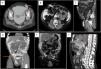

Dos de los bultomas abdominales se identificaron como hernias (fig. 1A), otro como fuga de dializado por el punto de entrada del catéter (fig. 1B), y en el cuarto no se visualizó el punto de fuga. Los casos de edema genital se identificaron como fuga de dializado en 3 ocasiones (figs. 1C y D) y como hernias inguinales en el cuarto (fig. 1E). En uno de los casos de defecto de ultrafiltración no se pudo confirmar un punto de fuga de dializado, y en el otro se demostró una comunicación pleuroperitoneal (fig. 1F).

A: Bultoma abdominal debido a hernia (flecha). B: Fuga de dializado por el trayecto subcutáneo. C: Fuga de dializado por persistencia de conducto processus vaginalis. D: Fuga de dializado por disección de planos a partir de pequeño punto de fuga (flecha). E: Edema genital por hernias bilaterales (flechas).F: Fallo de ultrafiltrafiltración por fuga peritoneo pleural (flecha=punto de fuga) (estrella=derrame pleural).